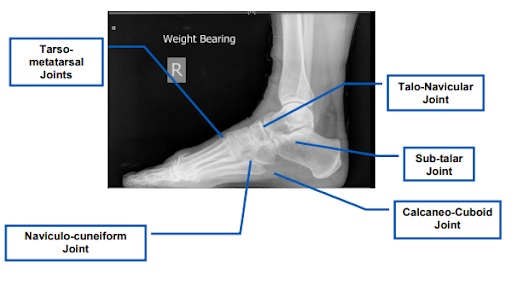

Joints which may be included in midfoot and hindfoot fusion surgery (Source: NHS).